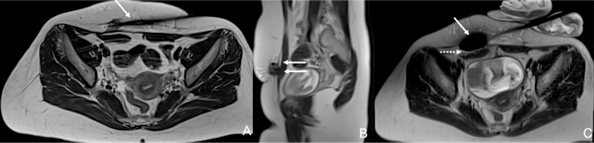

- The use of imaging (US and cross-sectional) to guide the intervention, which allows precise destruction of the AWE without provoking significant iatrogenic lesions to the surrounding non-target structures, mainly due to the intense use of ancillary protective measures (Fig .1).